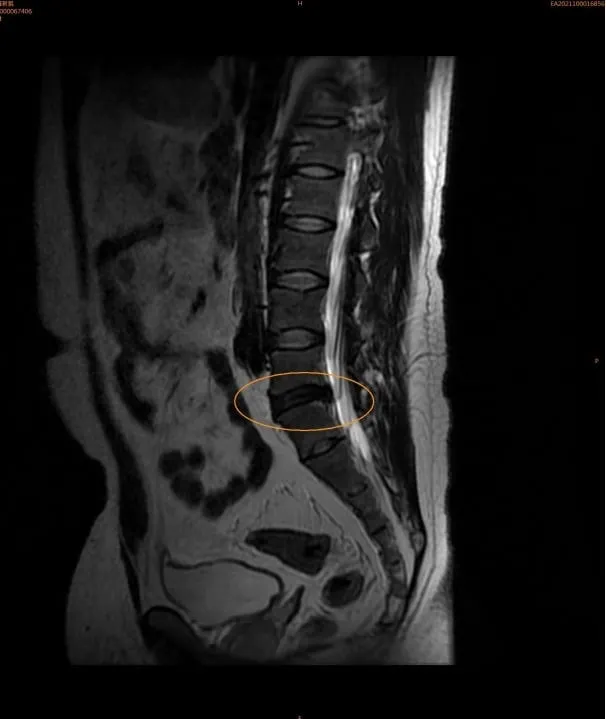

經個案同意分享,個案為頭痛個案,當時我幫個案弧動時,感覺腰椎第四與第五節可能有問題,但確切問題無法確定,稍微做放鬆處理後,頭痛症狀有改善一陣子,個案隨即至醫院檢查,X光檢查無異樣,但另一個影響檢查顯示,其腰椎第四第五節椎間盤已經退化。